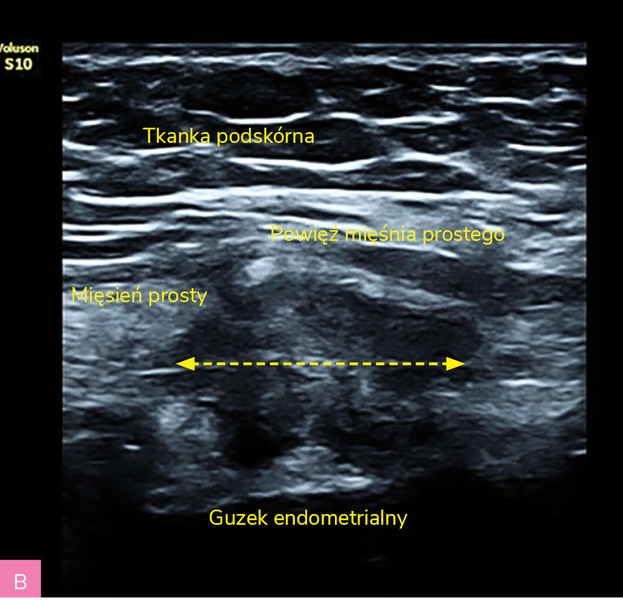

Rycina 2A, B. Obraz ultrasonograficzny zmiany endometrialnej powłok brzucha z typowym obwodowym skąpym unaczynieniem oraz odczynem wokół zmiany – obwodowe cechy włóknienia = hiperechogenna otoczka wokół guza (materiał własny autorki)

Charakterystyka wszczepów endometrialnych powłok brzucha (tab. 2; ryc. 1, 2):

- zmiany w większości hipoechogeniczne i heterogenne

- zmiany zwykle wykazują słabe unaczynienie

- średnica zmian wynosi między 5 mm a 5 cm, chociaż mogą osiągać znaczne rozmiary

- zmiany mają charakterystyczny spikularny (naciekający) obwód lub miejscowo nieregularny margines

- małe torbielowate obszary, głównie położone obwodowo – obraz drobnych torbieli krwotocznych, dające cień akustyczny

- obwodowe cechy włóknienia – hiperechogenna otoczka wokół guza.